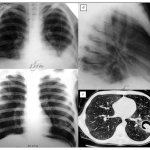

How to protect yourself and your baby during childbirth? There is no clear answer to this question. The main recommendations given to a pregnant woman are aimed at preserving the health of the baby and her own. A healthy lifestyle, moderate physical activity, weight control, timely visits to the doctor - a set of measures that prepares a woman in advance for a successful birth. Injuries to a newborn baby Various situations can lead to injuries during childbirth, for example, a discrepancy between the size of the baby's head (the largest part) and the size of the woman's pelvis, prolonged or, conversely, rapid labor. Those at risk for developing birth injuries include premature babies, as well as children who have suffered intrauterine hypoxia (oxygen deficiency) or asphyxia during childbirth. Some obstetric aids, such as the application of forceps or a vacuum extractor, unfortunately, can also cause certain injuries to the baby. Damage to soft tissues Prolonged standing of the baby in the birth canal can lead to the formation of a birth tumor. This is a potentially harmless condition that resolves on its own in the first 2-3 days of the baby’s life. A birth tumor has the appearance of a swelling of soft tissues and is located in the so-called presenting part of the fetus - that is, in the place that first passes the birth canal. Thus, a birth tumor can be localized on the head, face, buttocks and even the external genitalia. Cephalohematoma, or subperiosteal hemorrhage, is a deeper injury. It is localized in the presenting part of the head, more often in the projection of one bone. Cephalohematoma is often “covered” by a birth tumor, so it is not always possible to diagnose it in the first day of a baby’s life. Cephalohematoma always worries specialists! There are situations of ongoing hemorrhage under the periosteum, which leads to anemia in the child. Treatment tactics are agreed upon with the surgeon. Most often, the hematoma is evacuated by puncture (puncture). Soft tissue injuries also include abrasions, hemorrhages in the skin and subcutaneous tissue, which resolve on their own, requiring only antiseptic treatment and observation. Among muscle tissue injuries, the most common is tearing of fibers or complete rupture of the sternocleidomastoid muscle (“sternocleidomastoid” muscle), with the formation of a hematoma. Significant muscle damage can lead to acquired torticollis! Treatment tactics depend on the degree of damage and consist either of conservative measures (fixation of the head in the desired position, exercise therapy, physiotherapy) or surgical treatment. Bone tissue injuries This type of birth injury includes cracks and fractures of bones. According to statistics, fractures of the clavicle, humerus and femur occur more often. A fracture of the collarbone is manifested by the baby's anxiety and crying when feeling the injury site, and limited movements in the arm on the side of the injury. The doctor, by feeling the collarbone, can determine the compaction at the fracture site. When the humerus or femur is fractured, there is a sharp restriction of movements in the limb and a painful reaction of the baby to palpation and touch. The final answer is given by x-ray diagnostics. In treatment, it is important to compare the fragments and immobilize the limb. In most cases, the prognosis for this type of injury is favorable. Damage to internal organs and the central nervous system This type of birth injury is potentially very severe. In case of severe injury to internal organs, the newborn’s well-being suffers, lethargy and severe pallor are observed. In terms of diagnosis, instrumental research methods are often required: ultrasound, x-ray, computed tomography (CT). The most severe injuries include damage to the structures of the central nervous system. At risk are premature babies, children who have suffered severe intrauterine infection and hypoxia (oxygen deficiency). Such injuries are potentially life-threatening to the child. When making a diagnosis, data from neurosonography (ultrasound of brain structures) and other instrumental diagnostic methods are taken into account. It is important! The creation of perinatal centers on the basis of maternity hospitals and, in general, an increase in the level of medical care for newborn children has made it possible to significantly reduce the level of injuries during childbirth. An important condition for a successful delivery is the mother’s attention to her own health, timely visit to the doctor for examination and implementation of recommendations! Injuries to mothers During labor, the female body can also suffer. One of the purposes of maternity benefits is to protect the woman’s tissues: the cervix, perineum, etc. from injuries during the birth of the baby. An important step is making a fundamental decision - whether a woman can give birth on her own or whether a cesarean section is necessary. During independent childbirth, the doctor and midwife assess the degree of dilatation of the cervix, the intensity of contractions and help the woman decide when and with what force to push. Despite the provision of assistance, injuries to the mother's body still occur. These include injuries to the perineum (ruptures, tears, hematomas), vagina and cervix. Injury to bone tissue—the pelvic ring—occurs extremely rarely. It is important! How to avoid trauma during childbirth? Listen to advice! A large weight gain will not benefit the baby and will complicate the course of labor. Sometimes a woman is recommended to go to the maternity hospital in advance, for so-called prenatal preparation; you should not ignore this recommendation! During the birth process, the midwife holds the baby's head at the right moments, preventing it from injuring the maternal tissues. The woman in labor is given clear instructions: to push, not to push, to breathe correctly, etc. If necessary (overstretching of the perineal tissue), dissection is performed - episotomy. Subsequently, such wounds heal faster.